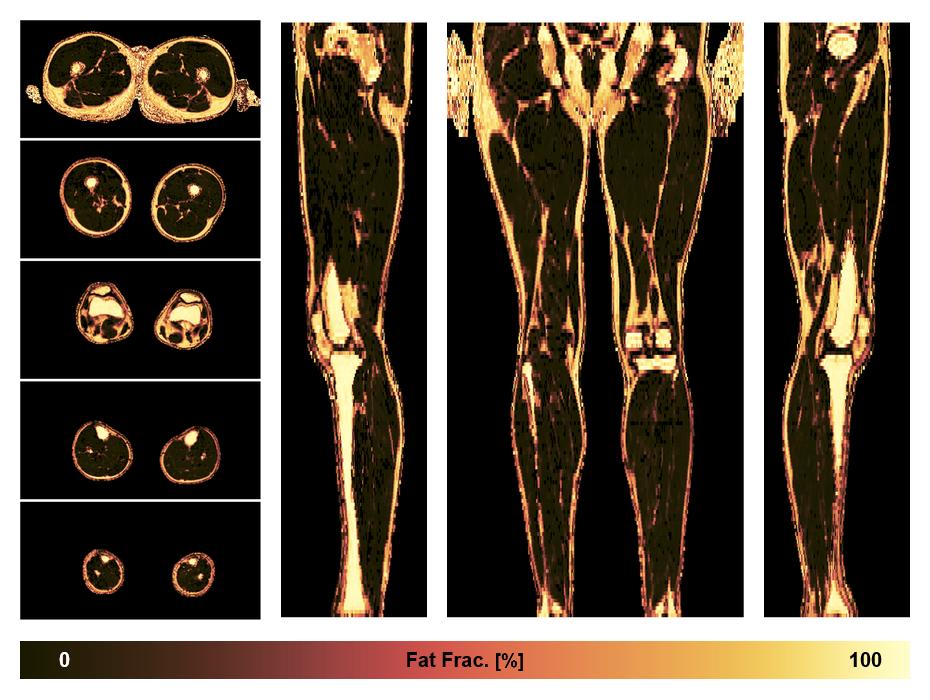

• Fat fraction

The fat fraction of the lower extremity obtained from the dixon reconstruction for muscle water fat quantification.